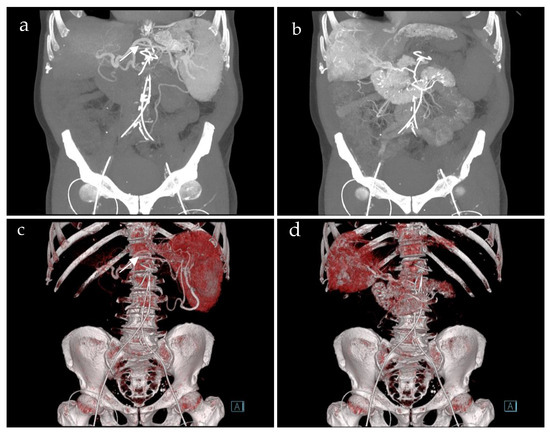

A total of 36 CT-SMPGs were performed in adult patients during an eight-year period. A total of 11 patients who suffered from acute PVT were excluded. Accordingly, 21 patients with chronic PVT who underwent CT-SMPG were included in this study (10 female, median age 47, 22–72 years). CT-SMPG indications were therapy planning of symptomatic PH with PVT in all patients. CT-SMPG was technically successful in all 21 cases. No procedure-related complications occurred. Figure 1 demonstrates an example of abdominal blood supply using CT-SMPG.

Figure 1. Coronal images of computed tomography spleno-mesenterico-portography of a 72-year old patient with portal hypertension showing the catheters in the splenic artery (a,c) (white arrow) and the superior mesenteric artery (b,d), both via the groin. Maximum intensity projection (a,b) and 3D models (c,d). Computed tomography splenoportography (a,c) detects the contrasted enlarged spleen, the splenic vein and extrahepatic portal vein. Computed tomography mesenterico-portography (b,d) shows the contrasted duodenum, liver and extrahepatic portal vein.